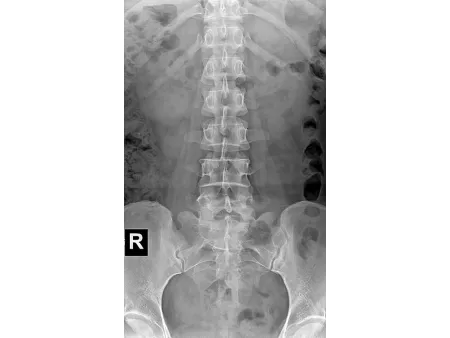

Este sistema radiográfico de doble columna está diseñado especialmente para salas DR, ofreciendo una estructura robusta y versátil que facilita el posicionamiento en distintos ángulos y alturas. Es ideal para realizar estudios detallados de cráneo, tórax, abdomen, columna lumbar y extremidades, y permite trabajar con proyecciones PA, laterales y otras imágenes clínicas estáticas con alto nivel de precisión.

Integra una pantalla táctil de 7 pulgadas que permite gestionar de forma intuitiva las funciones del equipo, junto con un sistema avanzado de adquisición digital que proporciona imágenes nítidas, consistentes y de alta resolución, adaptándose a los requerimientos de diagnóstico más exigentes. Está disponible en dos modelos: SHO-DDX03 y SHO-DDX04, ambos con varias configuraciones de potencia para ajustarse a distintos flujos de trabajo: 20 kW / 200 mA, 20 kW / 320 mA, 32 kW / 400 mA, 40 kW / 500 mA, 50 kW / 630 mA. Para aplicaciones clínicas más complejas que requieren mayor capacidad, el modelo SHO-DDX04 alcanza una potencia de hasta 65 kW / 800 mA, garantizando imágenes de alta calidad incluso en estudios que demandan una penetración más profunda o un nivel superior de detalle.